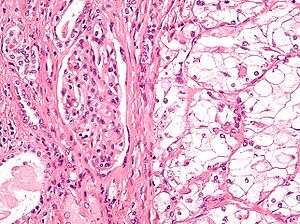

Micrograph showing the most common type of kidney cancer (clear cell renal cell carcinoma). H&E stain. | |

The two most common types of kidney cancer are renal cell carcinoma (RCC) and transitional cell carcinoma (TCC, also known as urothelial cell carcinoma) of the renal pelvis. These names reflect the type of cell from which the cancer developed.

Kidney cancer originates in the kidney in two principal locations: the renal tubule and the renal pelvis. Most cancers in the renal tubule are renal cell carcinoma and clear cell adenocarcinoma. Most cancers in the renal pelvis are transitional cell carcinoma.